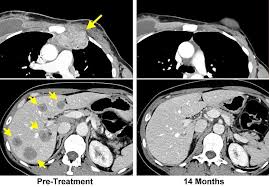

What Are The Symptoms Of Stage 4 Metastatic Breast Cancer - Metastatic Cancer When Cancer Spreads National Cancer Institute / We simply need to turn to corinne bruce's story to show how that is indeed the case.. Stage iv cancers have spread beyond the breast and nearby lymph nodes to other parts of the body. If the cancer has spread to the liver, symptoms may include nausea, fatigue, swelling of the feet and hands or yellowing skin. This is called metastatic breast cancer (mbc). Although stage 4 breast cancer is not curable, it is usually treatable and current advances in research and medical technology mean that more and more women are living longer by managing the disease as a chronic illness with a focus on quality of life as a primary goal. Stage 4 breast cancer is often diagnosed when the cancer recurs, although it may sometime be discovered at the initial diagnosis.

Metastatic means the cancer has spread beyond the breast and immediate lymph nodes to other organs or tissues in the body, most often the bones, brain, lungs or liver. Metastatic breast cancer most often spreads to the bones, brain, lungs and/or liver. Metastatic breast cancer is the most advanced stage of breast cancer (also known as stage iv), which means the cancer has spread beyond the breast to other parts of the body. These symptoms included depression, anxiety, sleep problems, fatigue,. Corinne came to hope4cancer treatment centers in february 2013 with a case of stage iv breast cancer that had spread to the bones.

Metastatic breast cancer is breast cancer that has spread beyond the breast and nearby lymph nodes to other parts of the body (most often the bones, lungs, liver or brain). Stage 4 breast cancer may develop these symptoms especially if the tumor is large or involves the breast skin. A sudden, noticeable new pain is the most common symptom of cancer that has spread to the bone. Stage iv cancers have spread beyond the breast and nearby lymph nodes to other parts of the body. It may also spread to the brain or other organs. The cancer has spread beyond the breast, underarm and internal mammary lymph nodes to other parts of the body near to or distant from the breast. Corinne came to hope4cancer treatment centers in february 2013 with a case of stage iv breast cancer that had spread to the bones. Metastatic breast cancer may grow silently in the body while you are completely unaware. Metastatic breast cancer most commonly spreads to the bones. These symptoms included depression, anxiety, sleep problems, fatigue,. Metastatic breast cancer most often spreads to the bones, brain, lungs and/or liver. They could be important for getting the treatment you need. Although breast cancer can spread to any bone, the most common sites are the ribs, spine, pelvis, and long bones in the arms and legs.

Metastatic breast cancer most often spreads to the bones, brain, lungs and/or liver. When symptoms do occur, what they are like and how often you have them will depend on the size and location of the metastatic tumors. Stage 4 breast cancer may develop these symptoms especially if the tumor is large or involves the breast skin. This is called metastatic breast cancer (mbc). When breast cancer spreads, it most commonly goes to the bones, liver, and lungs. Early on in metastatic liver cancer there might not be any signs or symptoms to alert you. Metastatic breast cancer is not a specific type of breast cancer, it's the most advanced stage of breast cancer. Corinne came to hope4cancer treatment centers in february 2013 with a case of stage iv breast cancer that had spread to the bones. If the cancer has spread to the liver, symptoms may include nausea, fatigue, swelling of the feet and hands or yellowing skin. If the cancer has spread to the lungs, symptoms may include shortness of breath, difficulty breathing, coughing, chest pain or fatigue. Chest pain other nonspecific systemic symptoms of metastatic breast cancer can include fatigue, weight loss, and poor appetite, but it's important to remember these can also be caused by medication or depression. Although breast cancer can spread to any bone, common sites are the ribs, spine, pelvis, upper bones of the arms and legs. For more than half of women who develop stage iv breast cancer, the bones are the first site of metastasis.

Stage 4 is the most advanced form of breast cancer.it is also referred to as metastatic breast cancer because the malignancy will have spread (metastasized) from the breast to other parts of the body, such as the bones, lungs, brain, or liver. But even though it's moved to other organs, it still behaves like. This is called metastatic breast cancer (mbc). Metastatic breast cancer after treatment for early or locally advanced breast cancer (stages i, ii and iii), it's possible for breast cancer to return (recur) and spread to other parts of the body (metastasize). Consequently, research into metastasis is of vital importance in overcoming deaths from metastatic breast cancers. Stage 4 breast cancer is often diagnosed when the cancer recurs, although it may sometime be discovered at the initial diagnosis. If the cancer has spread to the lungs, symptoms may include shortness of breath, difficulty breathing, coughing, chest pain or fatigue. Pain and fractures, when cancer has spread to the bone headache, seizures, or dizziness, when cancer has spread to the brain For more than half of women who develop stage iv breast cancer, the bones are the first site of metastasis. Although stage 4 breast cancer is not curable, it is usually treatable and current advances in research and medical technology mean that more and more women are living longer by managing the disease as a chronic illness with a focus on quality of life as a primary goal. As the cancer grows, you may experience liver swelling. These symptoms included depression, anxiety, sleep problems, fatigue,. When symptoms do occur, what they are like and how often you have them will depend on the size and location of the metastatic tumors.